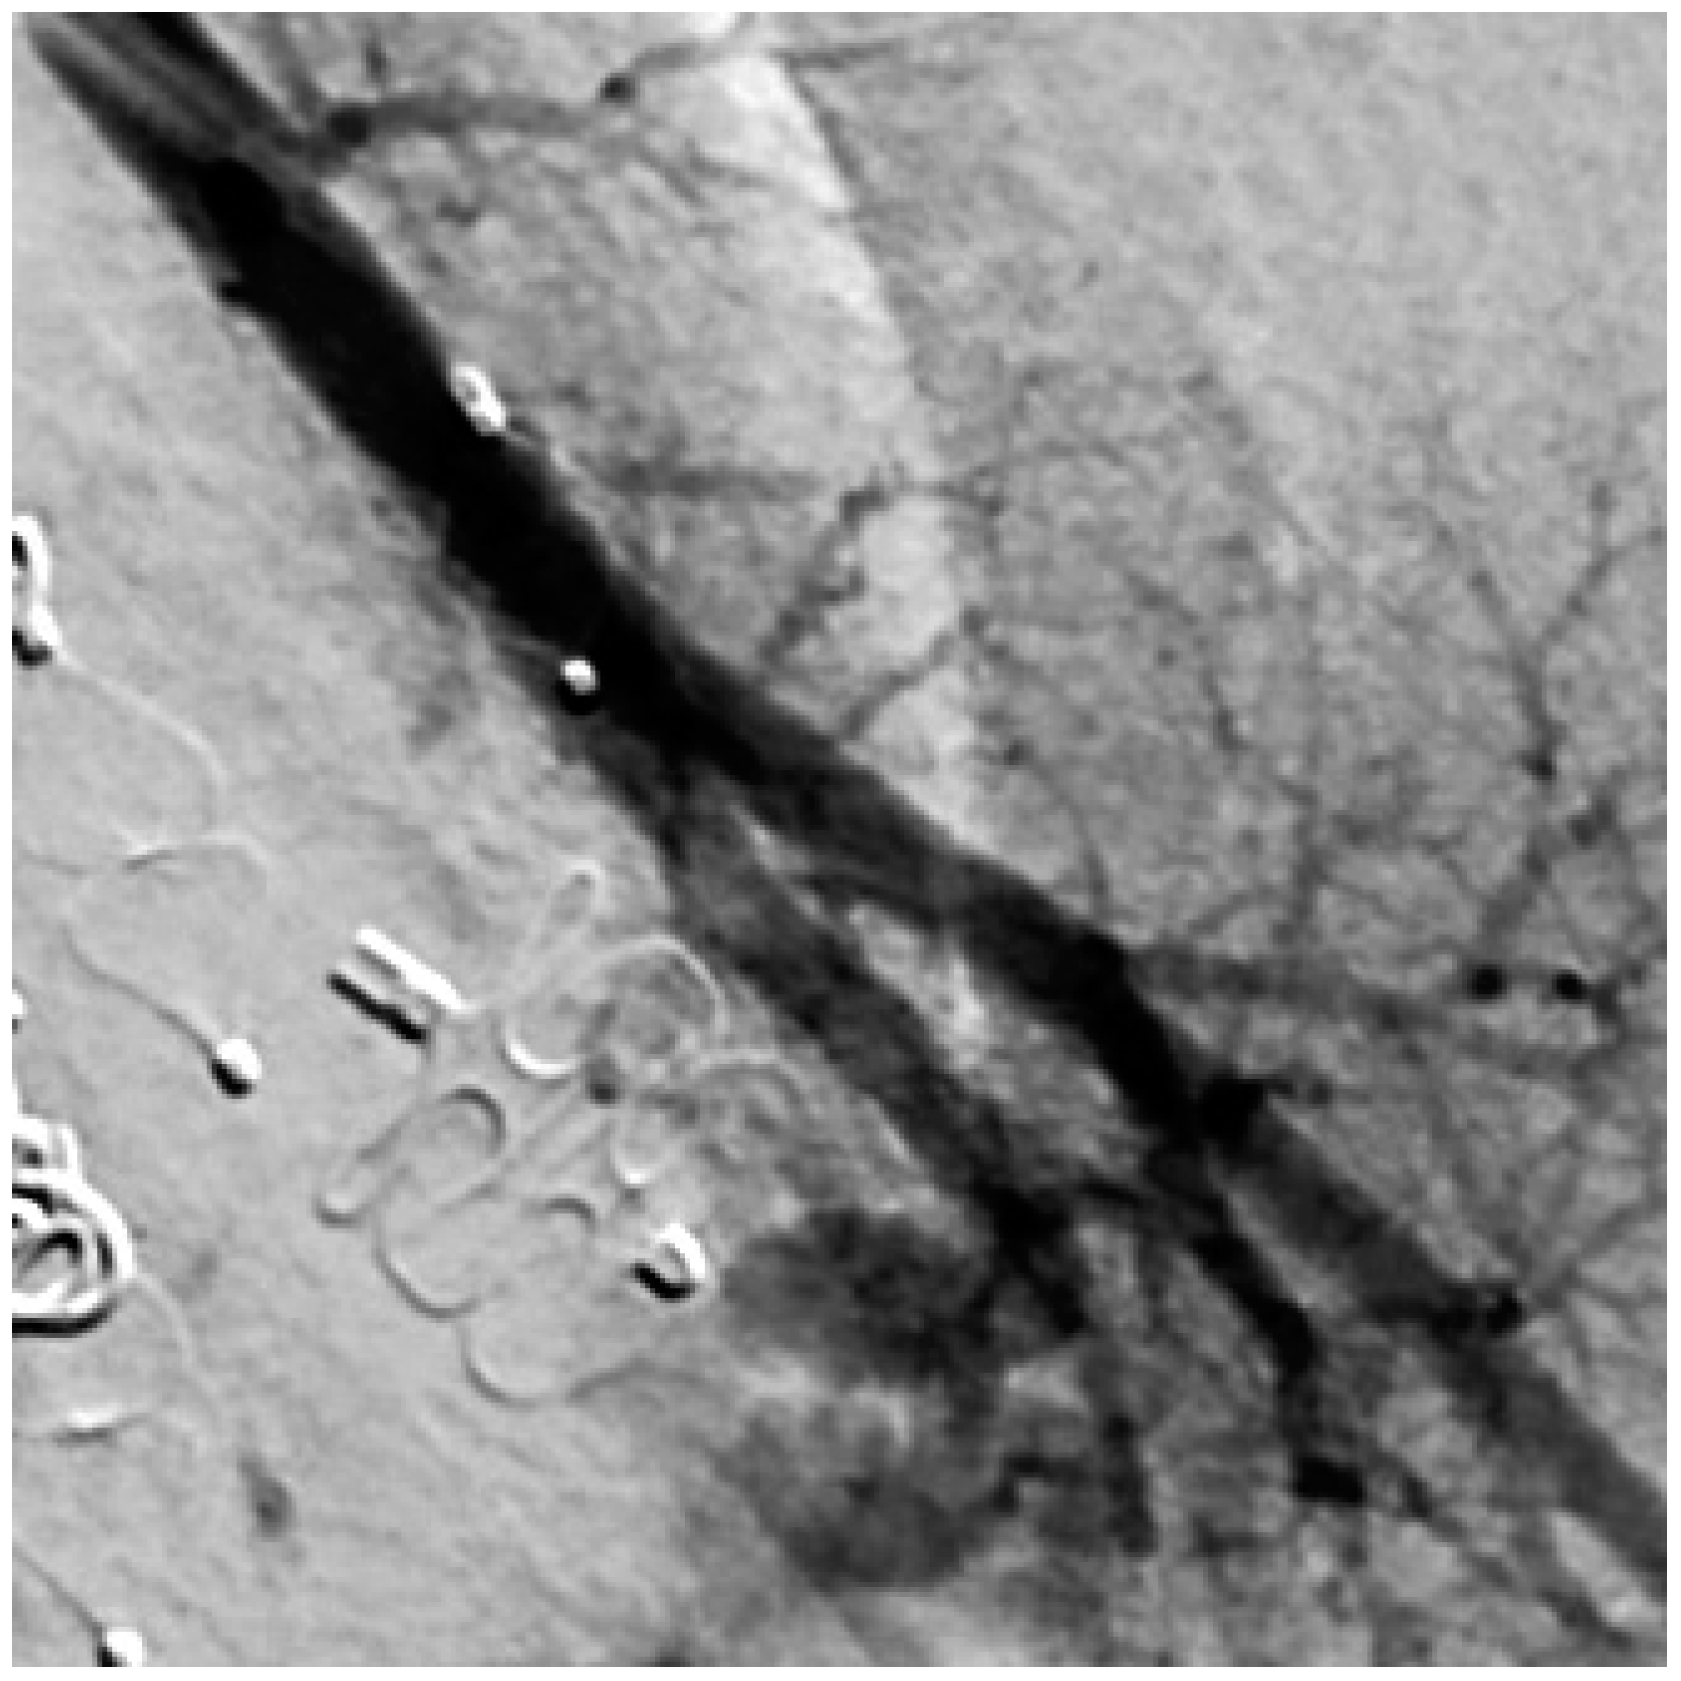

The perfusion of PAVM was observed in two externally embolized malformations, which were initially embolized by detachable coils in the aneurysm sac. In another patient, reperfusion could be attributed to an increase in the size of the feeding artery. During the initial embolization at the age of four years, the diameter was 1.5 mm and seven years later a diameter of 2.1 mm was determined during re-embolization. In another patient, the dilatation of the feeding artery in the area of the implanted embolization material was observed. This was already seen in the MRA performed and confirmed in a subsequent angiography. Furthermore, the fixation of the implanted coils in the arterial wall was evident in the DSA series. Figure 9 shows both the screening and the angiography images, with the open arrow in the MRA image showing the dilation of the feeding artery and the white arrows in the DSA image indicating the fixation of the implanted coils. The white line also emphasizes the dilatation of the feeding artery. It should also be emphasized that the embolization material completely filled the feeding artery during initial therapy and that the complete occlusion of the vessel was achieved.

Figure 9. MRA shows a dilatation of the feeding artery at the implantation site (left) and confirmation by an implemented DSA (right).